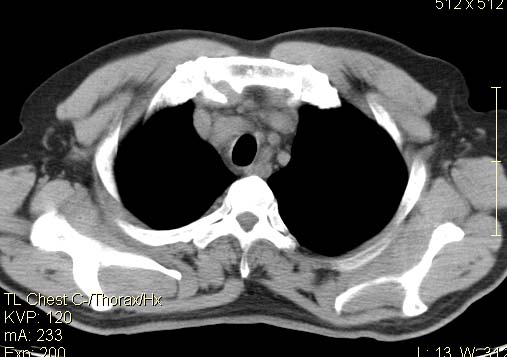

以下是引用qc80012345在2007-4-17 12:33:00的发言:[br]右肺下叶周围型肺癌伴肺门及纵隔内淋巴结转移;比较清楚。

以下是引用qingyuan在2007-4-17 14:19:00的发言:[br]右肺下叶外侧后段胸膜下区节结样病变、分叶、内可见空洞,壁厚薄不均,胸膜凹陷、肺门周围区纹理增粗、僵硬、并近似小结节样改变,肺门区软组织节结、纵膈淋巴结肿大,患者病史长、抗炎治疗无好转炎性改变基本排除,考虑:右肺下叶周围型肺癌伴纵膈及右肺门区淋巴结转移、肺内淋巴管受侵。